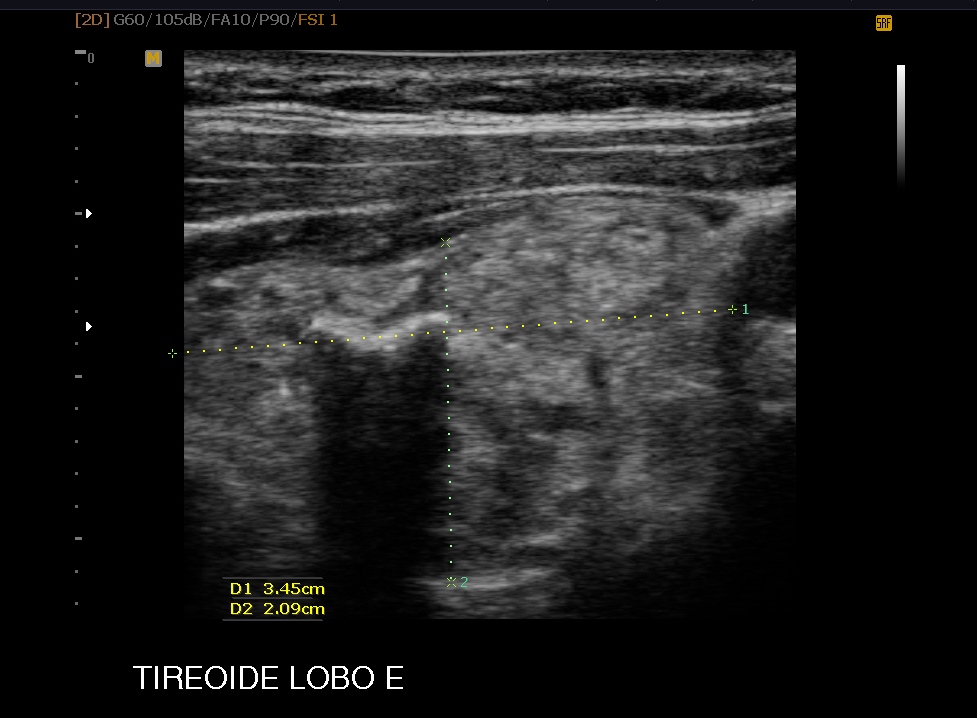

Realizamos biópsias com agulha de core e agulha fina para mama, e com agulha fina da tiroide com avaliação pelo método de Bethesda para quantificar a celularidade já na sala de exame, e posteriormente enviada aum excelente patologista.

Marcação pré cirurgica da mama com carvão ativado e agulhamento eda tireoide e linfonodos com carvão ativado.

Analise bioquica de tireoiglobulina em nodulos suspeitos de metastase cervical da tireoide e cisto tireoglosso.